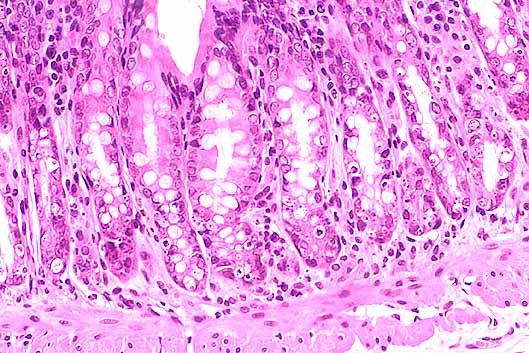

fig. 3

Figura 3.- Colon. Mucosa colónica con glándulas y lámina propia de aspecto normal. Discreta congestión de la submucosa. Escaso material inflamatorio intraluminal. (x40)